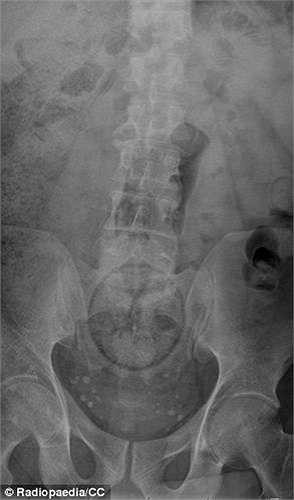

Hình ảnh X-quang là một trái cà tím đang nằm sâu trong trực tràng.

Các bác sỹ khó mà lý giải được tại sao nó lại đi qua được hậu môn của bệnh nhân và có xu hướng dịch chuyển lên trên.